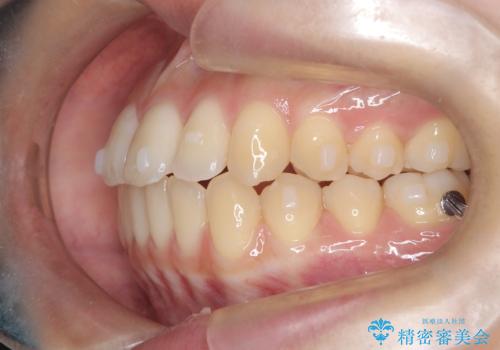

- 前歯のガタガタ(叢生)と、前歯が出ている(突出している)ことを気にされてご来院されました。精密な検査の結果、歯が並ぶスペースと、前歯を引っ込めるスペースの両方が不足していると診断。患者様のご希望に合わせ、透明で目立ちにくいインビザライン(マウスピース矯正)による治療計画を立案しました。スペースの確保は、奥歯全体を奥へ動かす遠心移動と、歯の側面をわずかに削る**IPR(歯間乳頭保護下ストリッピング)**を組み合わせて行い、前歯を効果的に引っ込めることを目指します。

今回の矯正治療では、透明なマウスピース型の装置インビザラインを使用しました。前歯を無理なく引っ込めるスペースを作るため、まず奥歯全体を後方へ移動させる遠心移動を実施。さらに、安全性が確保できる範囲で歯の側面をわずかに削るIPRを併用し、必要なスペースを確保しました。これらの処置により、前歯のデコボコが解消され、前に出ていた前歯も適切に引っ込みました。目立たない装置で治療を完結することで、叢生と突出感が解消され、機能性と審美性が向上した美しい口元を獲得していただけました。